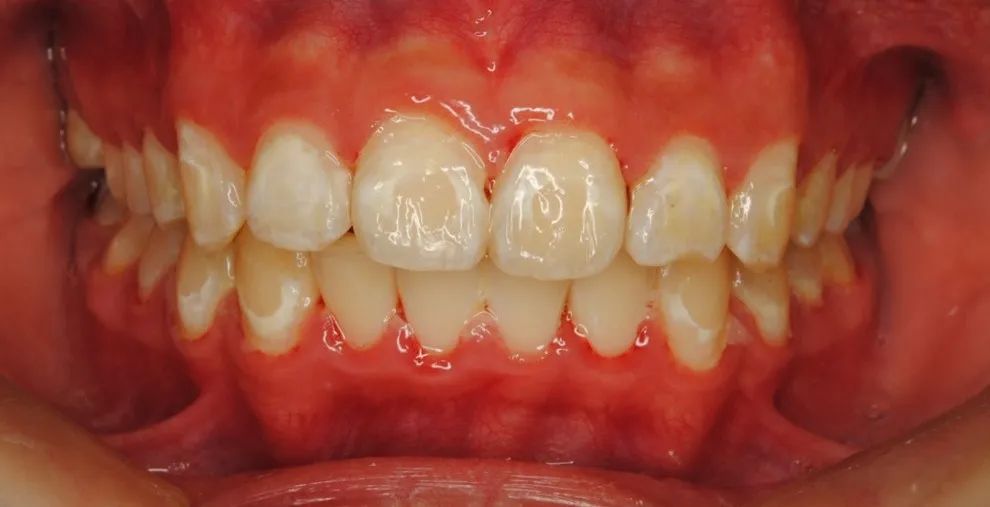

牙釉质脱矿(龋病) 来源:卓正医疗王羽医生病例